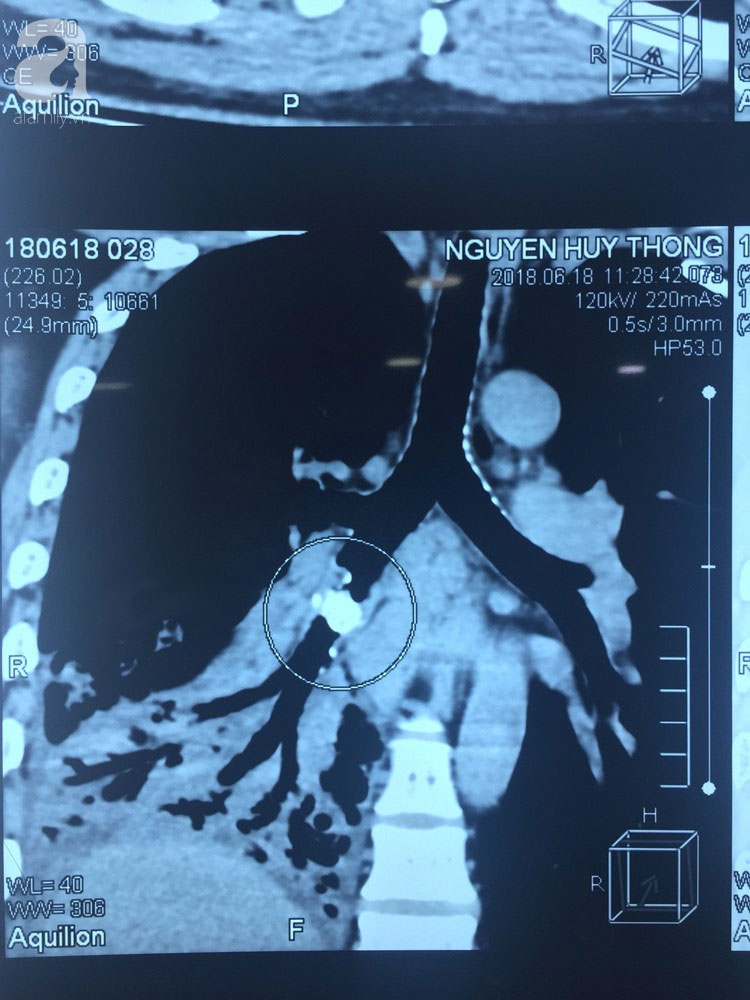

Sau khi thăm khám, ekip điều trị chẩn đoán anh bị viêm phổi. Tiến hành chụp CT phổi, các bác sĩ phát hiện một dị vật nằm trong phế quản của thùy dưới phổi phải. Đây chính là nguyên nhân gây ra các biến chứng viêm phổi cho bệnh nhân.

Bác sĩ Cao Minh Thông, khoa Ngoại Tim Mạch – Lồng Ngực của BV cho biết, thay vì như những trường hợp hóc xương khác bệnh nhân sẽ được tiến hành nội soi để gắp dị vật ra ngoài, bệnh nhân T. vì giữ trong người chiếc xương cá quá lâu trong suốt 5 năm nên dị vật này đã ghim sâu vào trong phần phế quản trung gian.

Điều này khiến phổi bị đông đặc và viêm mũ mãn tính, nội soi thông thường không thể gắp được. Vì vậy sau khi tổ chức hội chẩn, phối hợp chặt chẽ, các bác sĩ quyết định chọn phương án mổ hở, lấy dị vật xương cá ra ngoài và cắt phần phổi bị tổn thương.

Sau 2 giờ phẫu thuật, kíp mổ đã cắt thùy dưới phổi phải, lấy dị vật xương cá nằm trong phế quản ra ngoài. Sau mổ tình trạng sức khỏe người bệnh hồi phục tốt và đã được xuất viện.